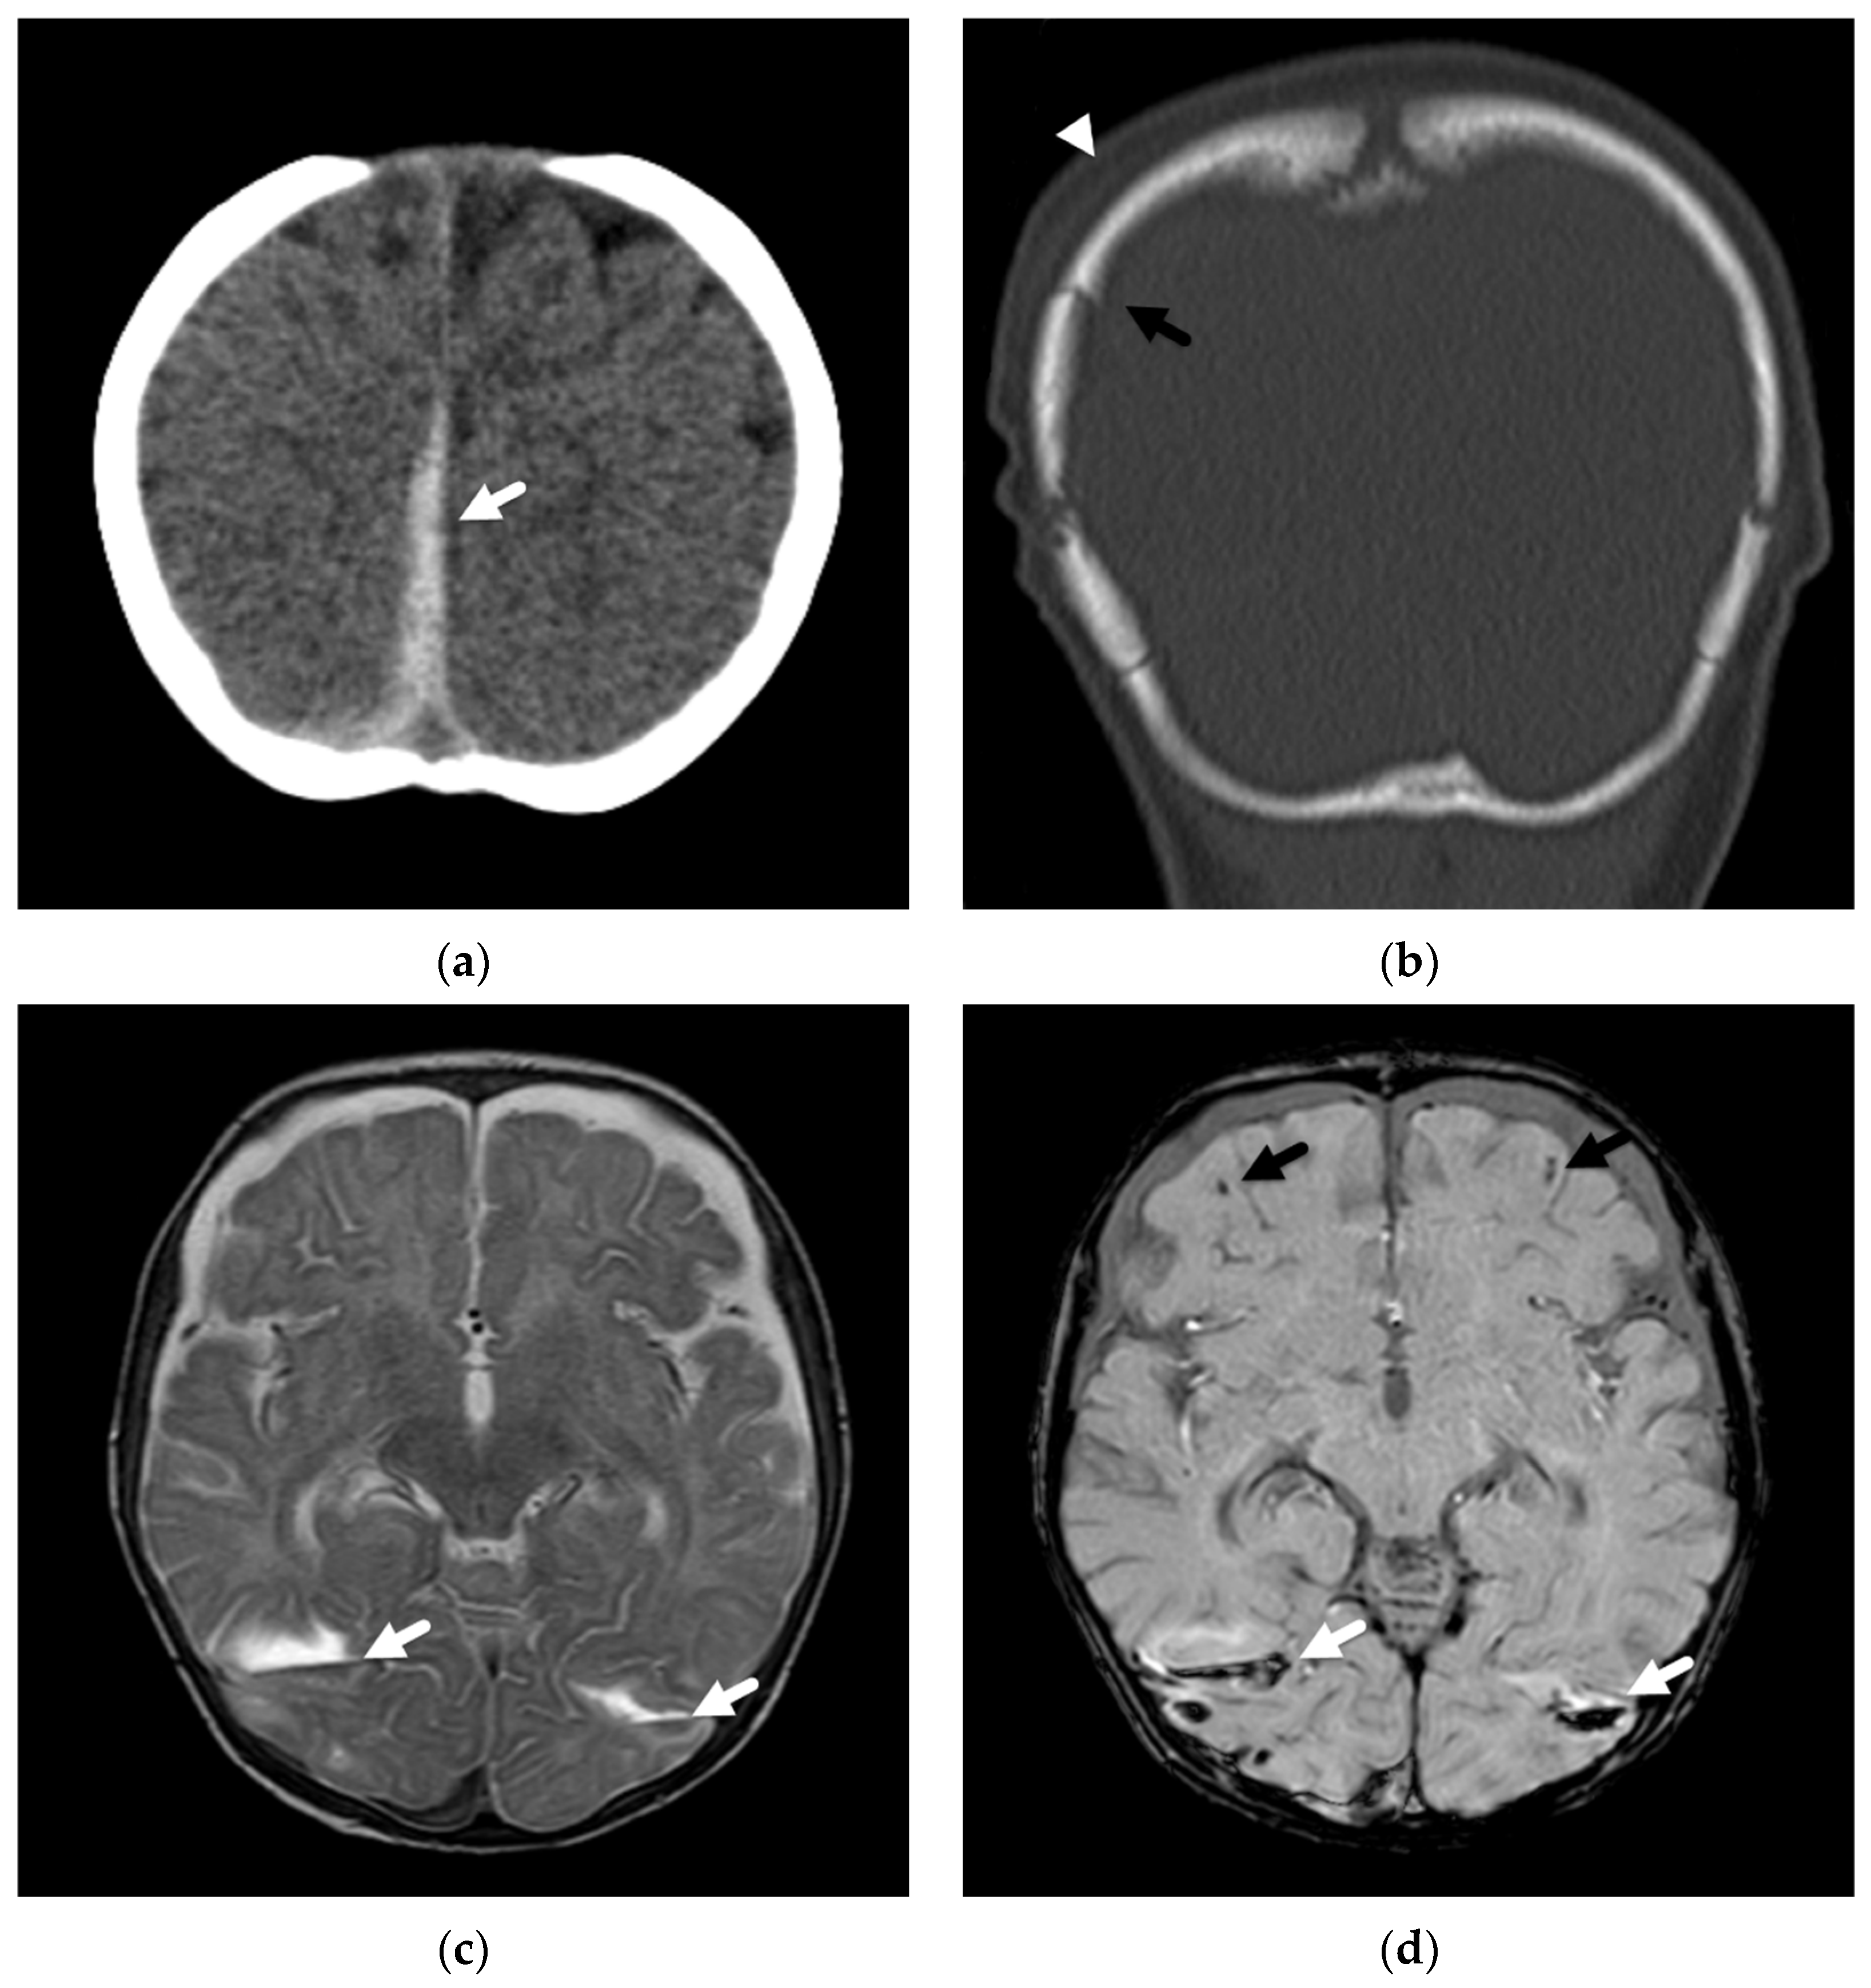

These diffuse, hemispheric patterns of injury/insult are observed in abusive head injury much more commonly than in cases of accidental pediatric head trauma [22,24], suggest permanent brain injury, and portend a poor outcome [22,23,24] (Figure 1). Except in cases of significant accidental trauma, such as pedestrians hit by cars or motor vehicle accidents, this type of injury is not found in children with more routine, household injuries [34], such as a short fall from a couch. In a comparative study looking at DWI in young children with abusive (n = 30) and accidental (n = 22) injuries, Ichord et al. [24] found that patients in their series with abusive injuries much more commonly demonstrated a pattern of restricted diffusion concerning for hypoxic-ischemic injury than those suffering accidental injuries (37% versus 9%). Nine of thirty abused patients demonstrated a predominantly diffuse pattern of parenchymal injury with a coexistent, small-volume subdural hemorrhage or other traumatic lesion compared with only 1/22 of accidental cases. Their patients with these diffuse insults tended to be younger in age, had greater acute and chronic neurologic abnormalities, and a higher likelihood of requiring longer-term inpatient rehabilitation.

Figure 1.

Subdural hemorrhage and subdural collections in an unresponsive 2-month-old male presenting with forehead bruising and respiratory depression. (a) Axial noncontrast head CT image demonstrates thin, high attenuation subdural hemorrhage along the posterior left occipital lobe (black arrow) and bilateral, low attenuation frontal subdural collections (white arrowheads). There is also subtle loss of gray-white matter differentiation bilaterally; (b) axial T2-weighted MR image on day 4 shows regions of decreased gray-white matter differentiation throughout both cerebral hemispheres with T2 hyperintense subdural collections (white arrowheads) and hypointense subdural hemorrhage posteriorly (white arrows); (c) axial b-1000 diffusion-weighted image demonstrates diffuse areas of abnormal, restricted diffusion (white arrowheads) in both cerebral hemispheres consistent with cytotoxic edema/hypoxic-ischemic injury; (d) apparent diffusion coefficient image shows corresponding regions of diffusion restriction predominantly in cortical and subcortical regions of both cerebral hemispheres (black arrowheads); (e) axial susceptibility-weighted image shows small, bilateral retinal hemorrhages (white arrows), confirmed clinically; (f) axial CT image at 2 month follow-up show diffuse brain parenchymal volume loss with now large, bilateral subdural collections (white arrows).

In another study, Zimmerman et al. [25] evaluated DWI in 33 abused infants and young children. The most common pattern of parenchymal insult, found in 13/33 (39%) patients, was of diffuse, restricted diffusion of the supratentorial cortex and white matter. Combined with their second most common pattern, which was present in 12/33 (36%), that of a more watershed or border zone distribution of restricted diffusion with primarily supratentorial but also infratentorial involvement, almost three-quarters of their patients had parenchymal imaging patterns suggesting diffuse hypoxic-ischemic injury/insult and resulting in permanent brain injury. These areas of restricted diffusion were not limited to isolated vascular distributions and were more extensive than focal impact or contusional injuries Figure 2.